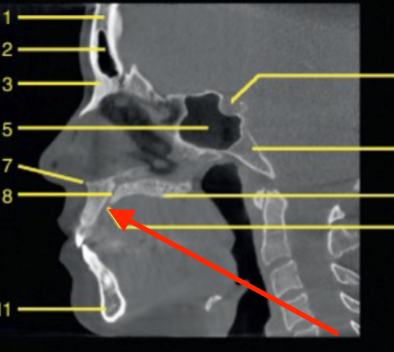

nasopharynx

identify the region indicated

oropharynx

identify 5

soft palate

identify the structure

tongue

epiglottis

C1

sella turcica